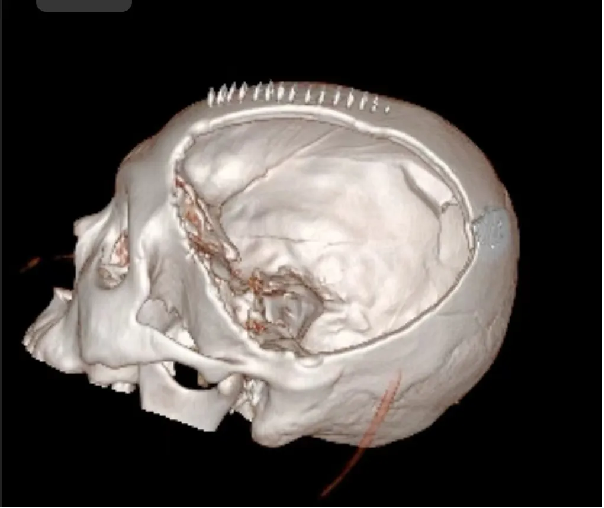

患者汪某,男性,66歲,因重症顱腦(nǎo)損傷,多發肋骨(gǔ)骨折,血氣胸,鎖骨骨折辦理入院緊急手術,醫院神經外科專家團隊為患者行開顱血腫清除+大骨瓣減壓術。手術順利,術後(hòu)恢複滿意。專家團隊將患者手術去除的顱骨骨瓣進行了清洗、滅菌後低(dī)溫冰凍儲存。

患者術後滿三個月(yuè)再次返院進(jìn)行顱骨缺損(sǔn)修補術,經過完善術前檢查、全(quán)科討論、做好充分手術(shù)準備後,武(wǔ)寧縣總醫院人民醫院院區神(shén)經外科團隊成功為患者完成(chéng)自體顱骨修補術(shù)。

術前: